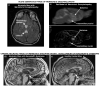

Figures